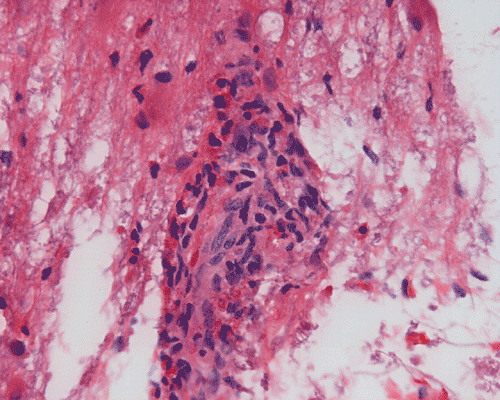

Panel A to E are MR images. Panel F and G are taken from intraoperative cytologic preparation. Panel H to M are taken from frozen section. Panel N and O are from paraffin section. These sections are stained by hematoxylin-eosin stain. Panel P is immunohistochemistry for neurofilament proteins. Panel Q is stained by Luxol fast blue-Periodic acid Schiff (LFB-PAS) stain.

Pathology:

| DIAGNOSIS: Eosinophilic myelitis. |

Pathology of eosinophilic myelitis

Eosinophilic myelitis is featured by lymphocytic infiltration accompanied by a varying intensity of eosinophils. Both the myelin and axons may be damaged. Axonal spheroids can be seen and indicate primary axonal damage rather than secondary damage following demyelination 14, 15. Destruction of axons in the lesion may well explain the relatively poor recovery of this condition. There is increase in eosinophils in CSF in the our under discussion. However, the CSF studies are normal in two previous studies 14, 15.

The eosinophils play an important role in causing the damages. Infiltration by eosinophils and depositions of activated products of eosinophils are commonly seen in atopic disorders, such as atopic bronchial asthma, allergic rhinitis and atopic dermatitis. The presence of atopic diathesis as well as eosinophilic cationic protein deposition suggests that atopy may represent one of the risk factors for developing eosinophilic myelitis. Eosinophilic cationic protein is one of the neurotoxic proteins released by activated eosinophils Eosinophil cationic protein and other products of eosinophils such as major basic protein have been shown to be neurotoxic. The infiltrating eosinophils may therefore well contribute to the neural damage.